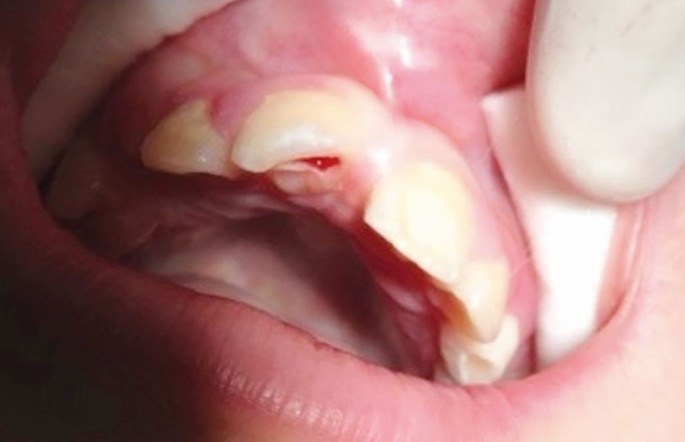

Delays in treatment may occur from athlete behaviour (late arrival, underestimating urgency, uncooperativeness) and healthcare factors (staff knowledge, accident and emergency department waits, triage). Effective care follows three phases: acute (within three hours), subacute (24 hours), and delayed (over 24 hours), as categorised by Andreasen et al.,43 to be followed alongside IADT guidelines34,35,36,37 for structured management (Table 3; Figures 10, 11, 12, 13, 14, 15, 16 and 17).

Intrusion of a central incisor, loss of a lateral incisor and laceration of the gingivae following trauma